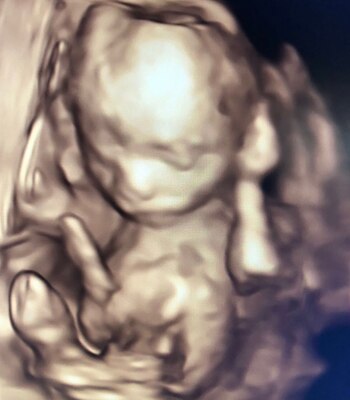

En una de las fotos de la ecografía 4D que posteó, exresó: "Hoy cumple 18 semanas, ya mide como un pimiento y me regalo estas imágenes; es la primera ves que le conozco la carita y no quería dejar de compartirlo con ustedes!".